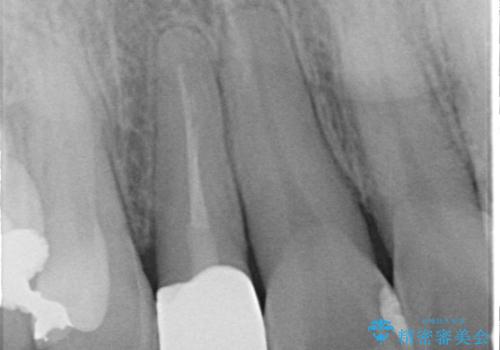

- 「前歯の見た目が気になる」を主訴に来院された患者様です。

失活歯による歯の変色とCR(コンポジットレジン)の劣化による審美不良でした。

オールセラミッククラウンで治療し見た目の改善を行いました。

まず劣化したCRと虫歯を除去した後、仮歯に置き換えました。歯のマージンラインを綺麗に削り光沢が出るまで研磨した後にオールセラミッククラウンの型取りを行っています。